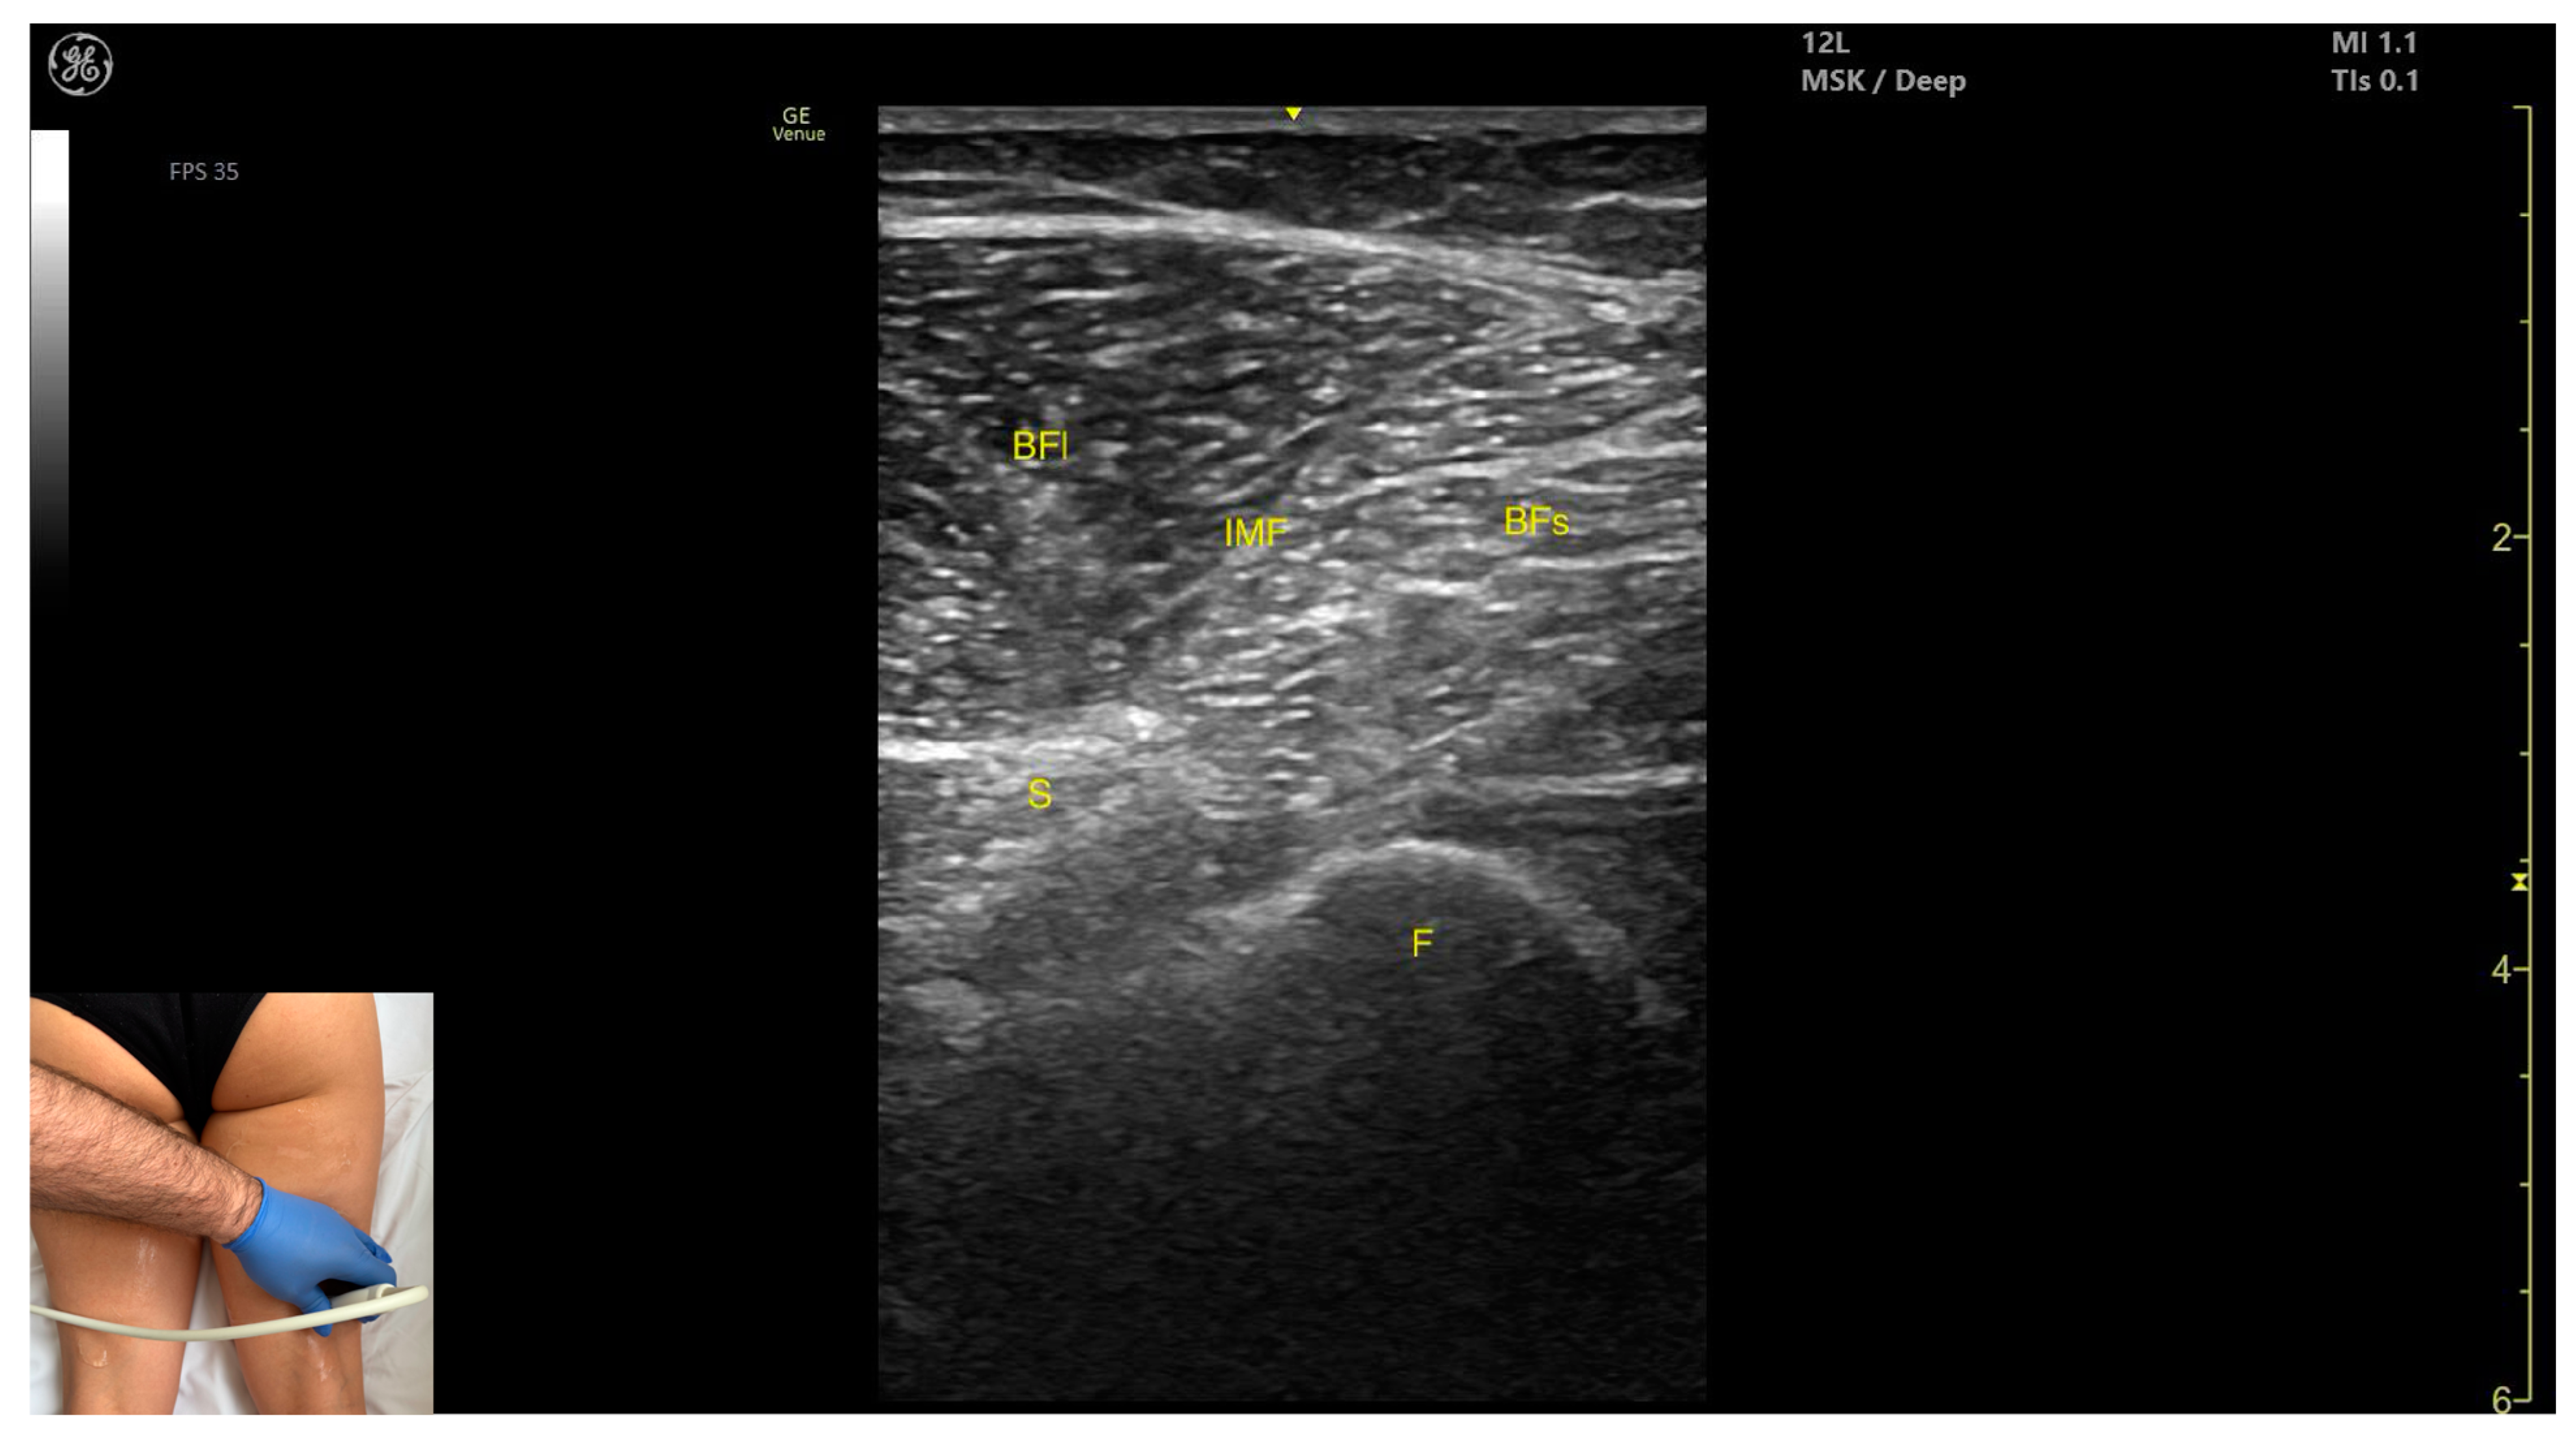

3.11. Biceps Femoris (BF)

3.11.3. Key Ultrasound Landmarks

- Muscle morphology: It has two heads: the long head (medial) and the short head (lateral), which can be approached individually, separated by an intramuscular fascia.

- Muscle position: It appears as a superficial muscle mass and is the most lateral muscle in the posterior (flexor) compartment of the thigh at this level. The long head lies adjacent to the sciatic nerve, which runs underneath the muscle.

- External fascia: A pronounced fascia separates the BF from the subcutaneous plane, and from the vastus lateralis and semitendinosus, which is relevant during BoNT-A injections.

- Dynamic evaluation: During dynamic evaluation, scanning proximally toward the hip joint, the long head increases in thickness while the short head decreases. At the mid-thigh, the short head disappears, and the long head reaches its maximum thickness. Scanning distally toward the knee joint, the short head increases in thickness, and the long head decreases. Muscle contraction is visible during hip extension, external rotation, knee flexion, and the external rotation of the leg.

3.11.4. Clinical Implications and Injection Strategy

- 15–30% of the reference line for the short head;

- 50–60% of the reference line for the long head.

- For the short head, the transducer is placed transversely on the distal third of the posterior-lateral thigh;

- For the long head, the transducer is placed transversely at mid-thigh level on the posterior-lateral thigh.

| BF | Biceps femoris (muscle) |

| BFs | Biceps femoris (muscle) short head |

| BFI | Biceps femoris (muscle) long head |

| IMF | Intramuscular fascia |

| S | Sciatic (nerve) |

| Biceps Femoris | Distal third of posterior-lateral thigh (short head); mid-thigh for long head | Sciatic nerve (under long head) | Transverse scan at two levels on posterior thigh | Identify and differentiate long and short heads and avoid nerve injury |